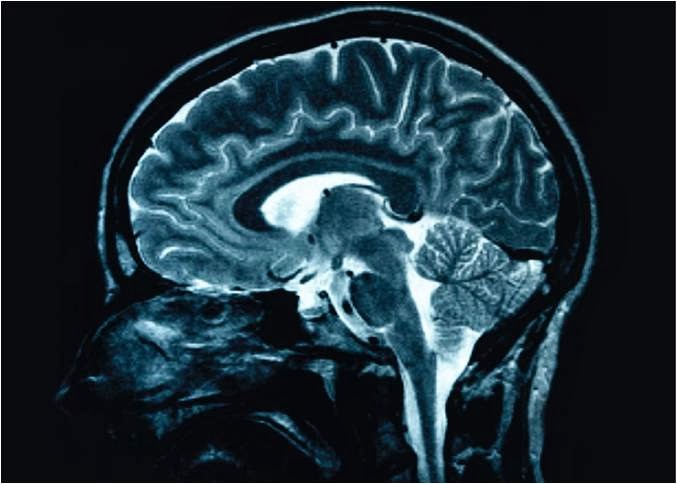

برخی از کودکان نیاز به تکرار کردن آزمایشاتی دارند که شامل موارد زیر است: